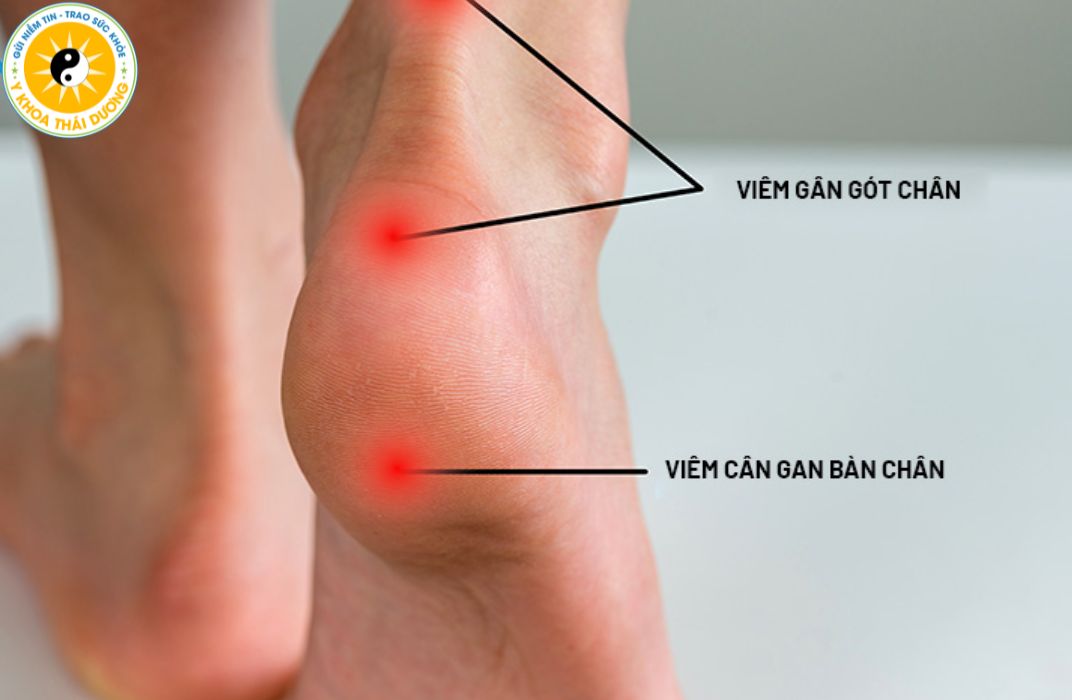

Viêm gân: Nguyên nhân, triệu chứng và phương pháp điều trị

Viêm gân (Tendinitis) là bệnh lý cơ xương khớp xảy ra rất phổ biến ở...

Viêm gân: Làm sao để điều trị dứt điểm và tránh tái phát?

Viêm gân là tình trạng tổn thương phổ biến gây đau nhức và hạn chế...